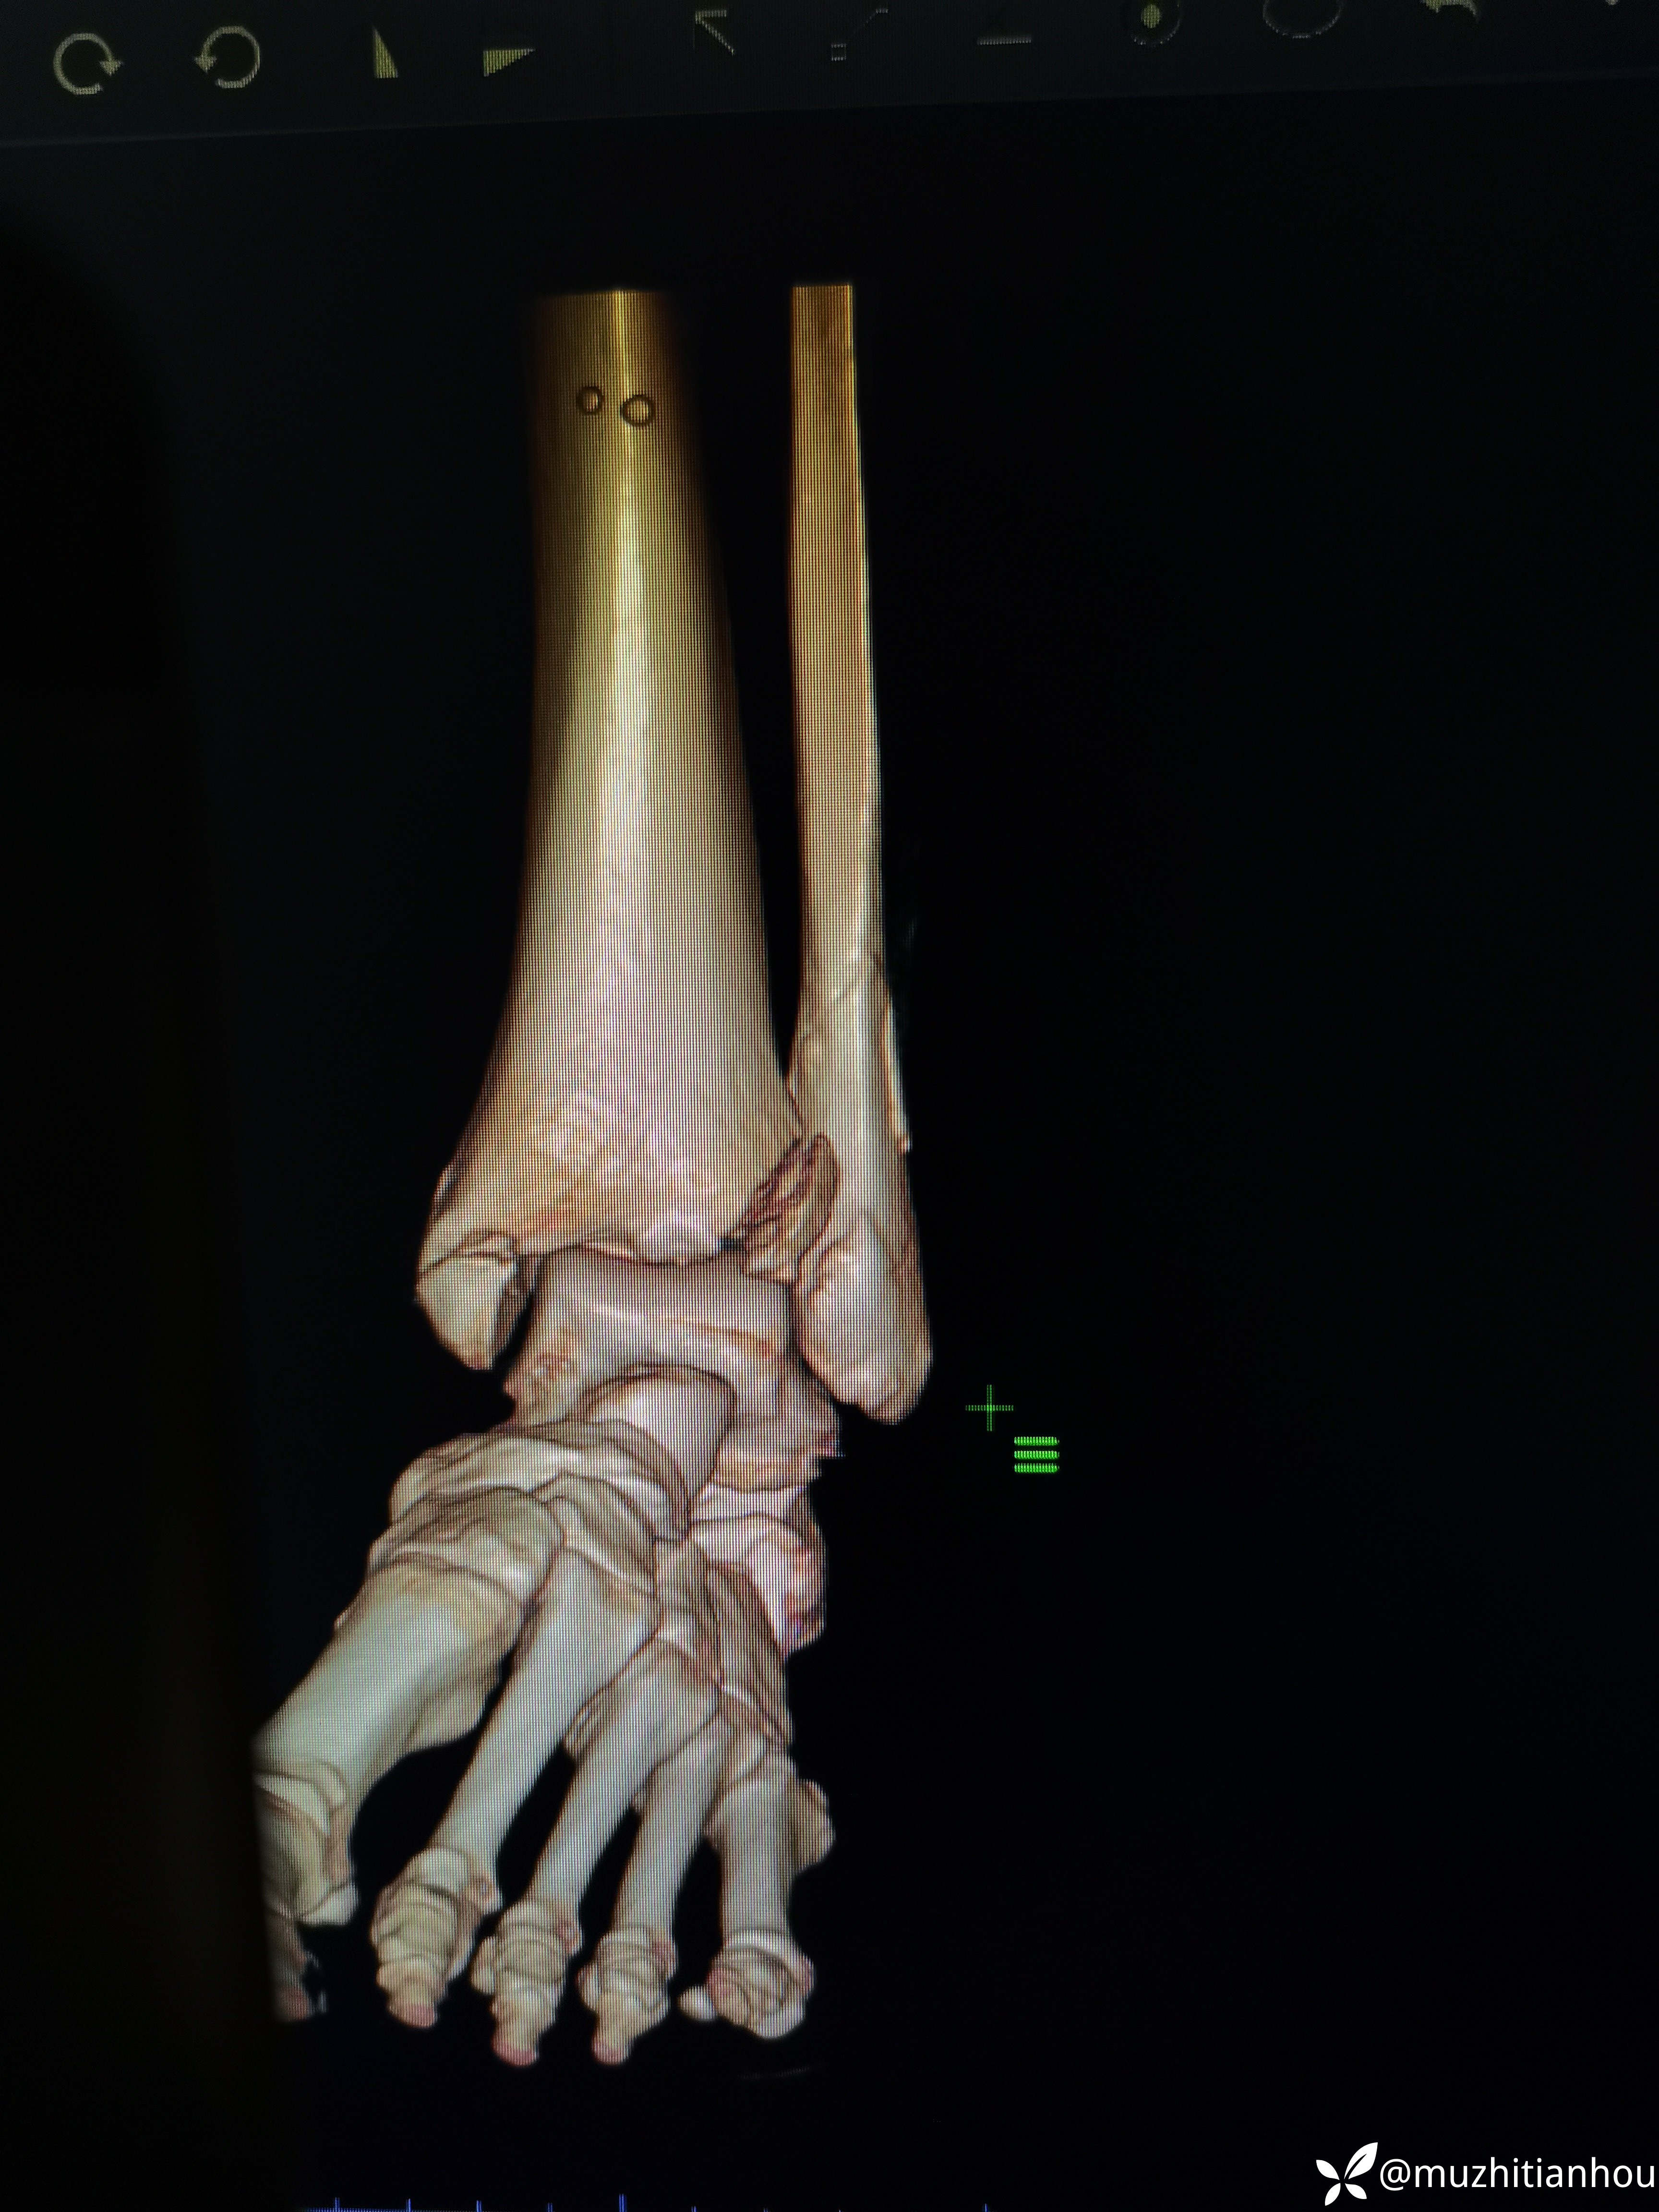

讲明白道理后取得患者信任,入院做了三维CT真像慢慢浮出水面,看到这个您是不是觉得收获很大

后踝骨块无需处理

三维重建来的更直观,Tillaux骨块的分型和处理选择大家是否铭记在心呢?我想大多数人跟我差不多,回头去复习下吧。收获会很大